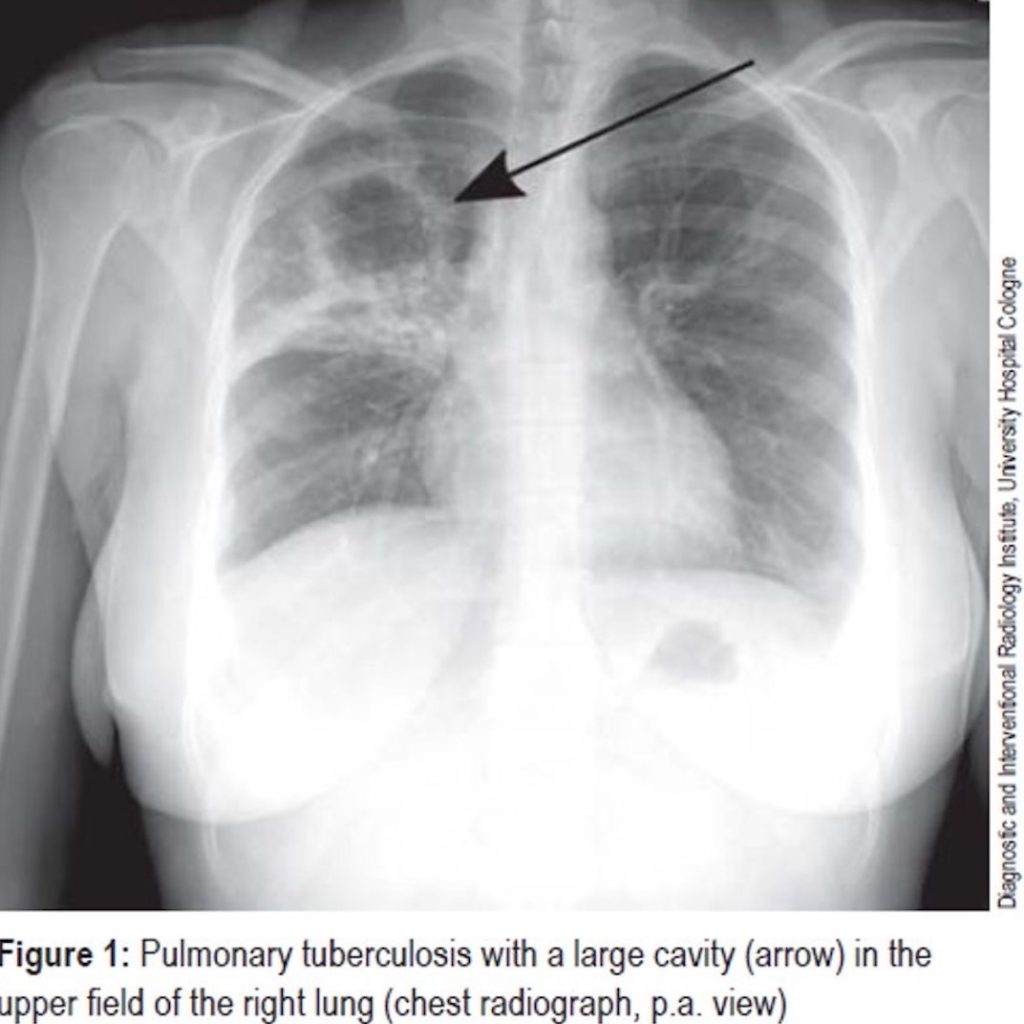

25 year old male presents with chronic cough and fatigue, now febrile Swiss Cheese Lungs finally, the so called “swiss cheese sign” is used to indicate the appearance that the lung develops with pulmonary tears and pneumatoceles—filled with air and/or fluid after traumatic events. The pneumatocele appears as a “hole” within the lung parenchyma that looks like swiss cheese. the term swiss cheese has also been used for the description of pneumatoceles formed. Swiss Cheese Lungs.